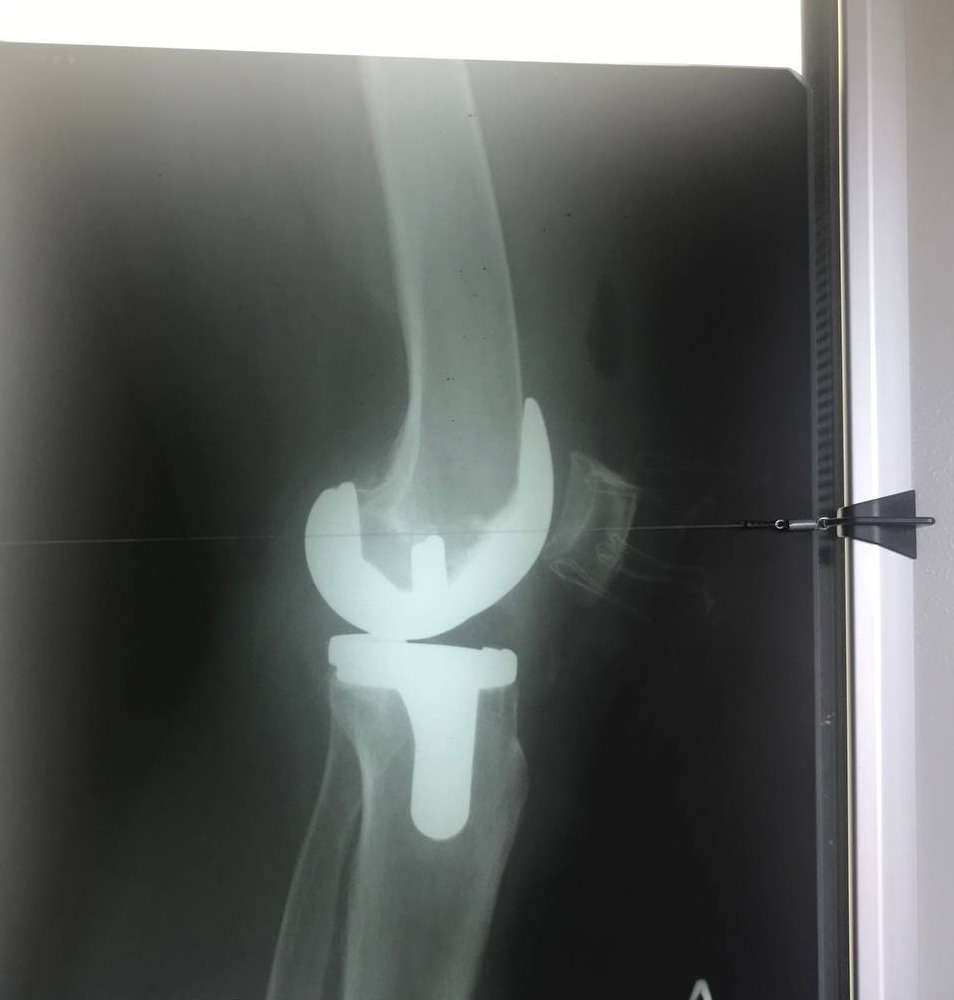

За інформацією Охтирської міськради, співпраця розпочалася із проведення операцій на хребті найсучаснішим методом. Завідувач відділенням ортопедії та травматології Університетської клініки д-р. мед наук Дмитро Петренко спільно з лікарем відділення Дмитром Демченком вже провели в Охтирці дві операції на хребті. У одного пацієнта була травма, у іншого – грижа хребта. Оперативні втручання пройшли успішно і без ускладнень.